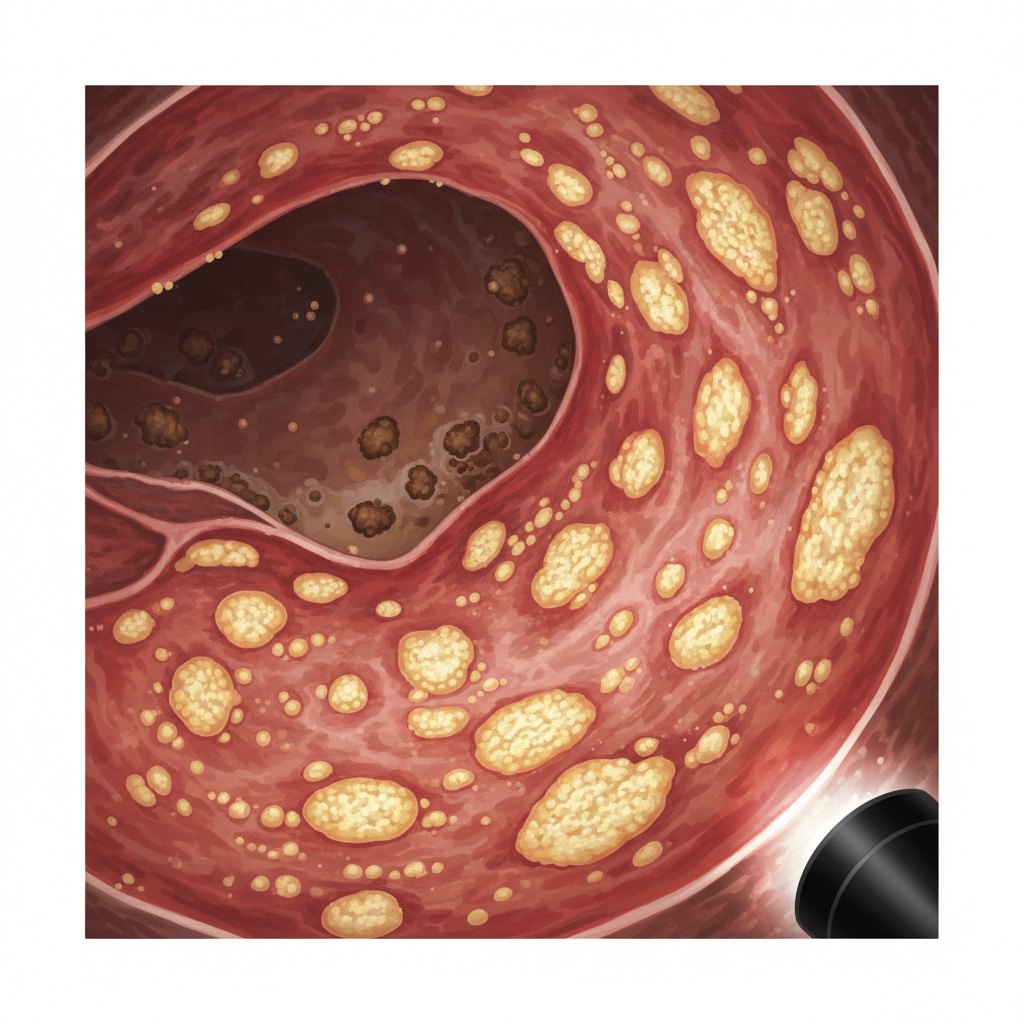

Endoscopic Confirmation

Flexible sigmoidoscopy (9 Jan)

Pseudomembranous colitis

Visual diagnosis supersedes toxin assays

High-volume diarrhoea causes toxin dilution

• c-diff toxin -ve, PCR +VE, Pseudomembranous colitis<br>• Per BC Cancer / CCO, visual pseudomembranes override negative toxin assays<br>• High-volume secretory diarrhoea → toxin dilution